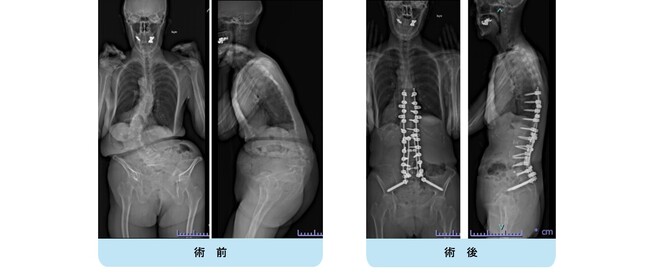

思春期特発性側弯症の全脊椎レントゲンで背骨が大きくSの字に曲がっています。最も曲がっている箇所は80°で、高度側弯に分類されます。後方からの脊柱側弯矯正術で真っ直ぐになっています。

また、側弯の患者さんは一般的にフラットバックと言って背骨の生理的後弯(背中の丸み)が失われています。この症例も胸椎後弯角は5°で典型的なフラットバックを呈しています(正常は20°~30°程度です)。この影響は頸椎の形態にも影響を及ぼし、この症例も頸椎が既に後弯(正常は前弯)しています。(黄色矢印)

ストレートネックという頸椎の前弯が消失して頸部の愁訴が出現する病態は広く知られていますが、更に変形が進行した頸椎と考えて下さい。

以前はこのフラットバック(生理的胸椎後弯の消失)を治すことは困難でしたが、当院では手術方法の様々な工夫により生理的胸椎後弯の復元を行っております。この症例は術後に胸椎後弯角が26°と改善しており、生理的な胸椎後弯が形成されています。さらに頸椎後弯にも良い影響を及ぼし、術後は頸椎前弯化が得られつつあるのが分かります。(黄色矢印)

他、側弯変形は必ず大なり小なりの回旋変形を伴います。脊柱の回旋変形は胸郭(肋骨)の回旋につながり、これにより側弯の患者さんは背中の片方が出っ張っています(多くは右)。リブハンプと言いますが、脊柱変形矯正によりこの回旋変形も改善します。この症例も術前に肋骨がかなり隆起していますが、術後にこの隆起がかなり減じているのが分かります。(赤矢印)